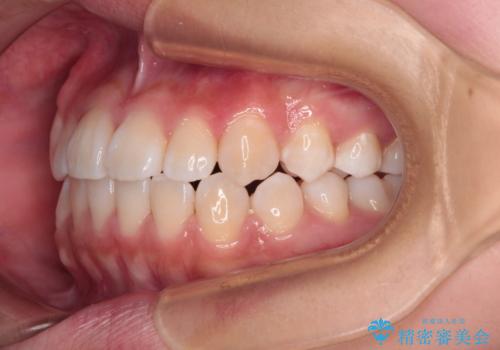

前歯のデコボコを楽して改善 ワイヤー装置による矯正治療

- メタルブラケット

- 1年2ヶ月

- 前歯のデコボコを治したいとのことで来院された患者様です。

インビザラインによるマウスピース矯正も適用となる歯列でしたが、できる限り楽して、短期間で治したいとのことで、ワイヤー装置にて矯正治療を行うこととしました。